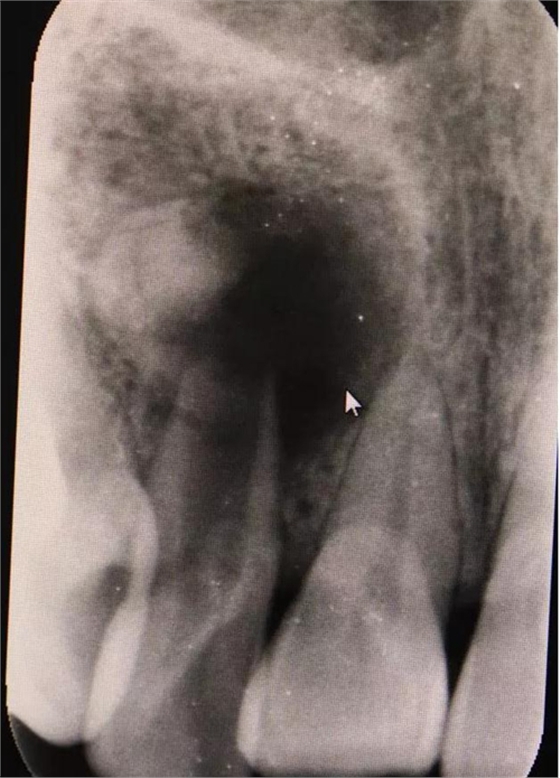

圖1.術(shù)前的根尖片影像檢查:12根管粗大、根尖未形成。根尖下方有一橢圓形囊腔,囊內(nèi)有牙。